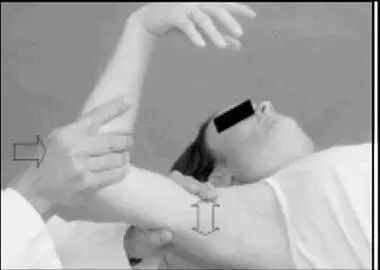

主要用于检查前方不稳。 病人仰卧位,检查者一手握住病人的前臂,另一只手在后方托起病人的上臂,轻而慢地外展和外旋上臂,当病人感到肩后疼痛并有即将脱位的预感而产生恐惧,拒绝进一步外旋时,恐惧试验阳性。在肩关节外展外旋的同时时对肱骨头再施加向前的应力,可进一步引发患者恐惧感或疼痛,为加强试验阳性。在做恐惧试验后,于肱骨头施加向后的应力,当病人恐惧感减轻或消失,即复位试验阳性。

a.恐惧试验;b.恐惧试验加强试验;c.复位试验;d.复位试验加强试验